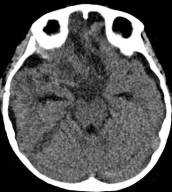

病例二:患儿女性,7岁,主因头痛2年,精神差1个月收入院。入院时头CT见典型的“超大型”颅咽管瘤,直径约9厘米,见图6。

图6.CT显示囊性颅咽管瘤

白色三角显示肿瘤边界

患儿入院后第三天,病情恶化,意识不清,急诊行肿瘤囊穿刺引流术,引流出囊液约200毫升,引流后患儿精神立即好转,肿瘤体积减小,引流手术切口设计及引流后CT见图7、图8。调养7天后在全麻下行开颅手术切除肿瘤,经过10个小时的努力,完全切除肿瘤,术后患儿清醒,语言交流正常,左侧上下肢肌力稍弱。患儿经历一系列的并发症,如电解质紊乱、脑水肿、癫痫发作等,共计住院47天后出院。术后CT见图9。